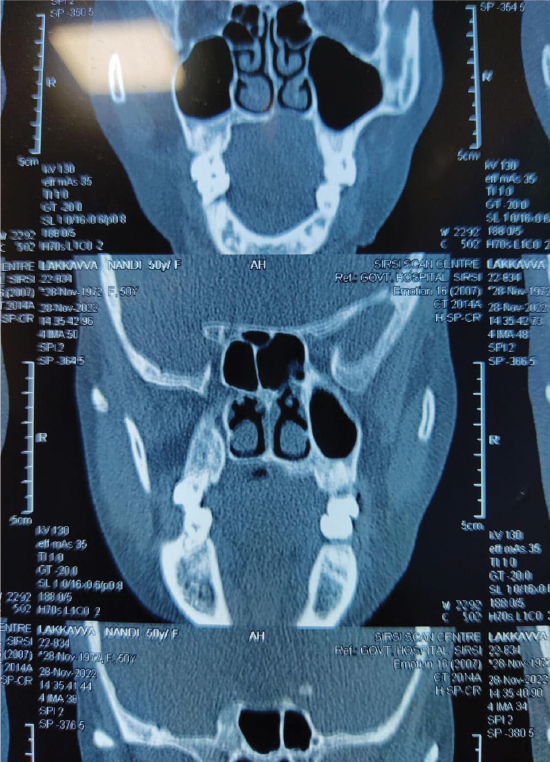

The patient was then counseled for surgery after getting a plain computed tomography (CT) scan (Fig. 2) to rule out any erosion of the palate. The scan also revealed a soft tissue mass in the hard palate region.

Figure 2. CT scan film of the patient shwoing the hard palate region.